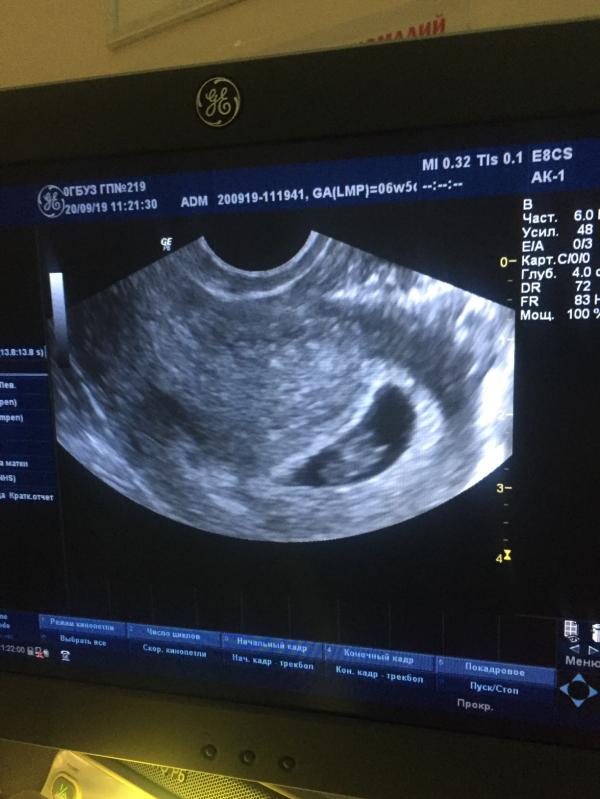

КАК ПРОХОДИТ МОЯ БЕРЕМЕННОСТЬ?🤰🏼

Я долго думала писать мне этот пост или нет, но все-таки решилась)

По началу было не понятно что со мной происходит, часто хожу в туалет (по маленькому) и тянуло дико низ живота , как при менструации , но эти дни так и не приходили , и решили сделать тест. Думали надежды напрасны, может со мной что-то не так , может застудилась?Мы долго планировали нашего сыночка, полгода попыток и вот свершилось , в конце августа тест показал ➕, радости нашей не было предела🤪